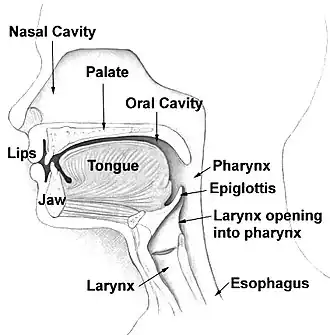

The oropharynx, at the back of the mouth, forms a circle and includes the base of the tongue (posterior third) below, the tonsils on each side, and the soft palate above, together with the walls of the pharynx, including the anterior epiglottis, epiglottic valleculae and branchial cleft at its base. The oropharynx is one of three divisions of the interior of the pharynx based on their relation to adjacent structures (nasal pharynx (nasopharynx), oral pharynx (oropharynx) and laryngeal pharynx (laryngopharynx – also referred to as the hypopharynx), from top to bottom). The pharynx is a semicircular fibromuscular tube joining the nasal cavities above to the larynx (voice box) and oesophagus (gullet), below, where the larynx is situated in front of the oesophagus.[31]

The oropharynx lies between the mouth (oral cavity) in the front and the laryngopharynx below, which separates it from the larynx. The upper limit of the oropharynx is marked by the soft palate and its lower limit by the epiglottis and root of the tongue. The oropharynx communicates with the mouth, in front through what is known as the oropharyngeal isthmus, or isthmus of the fauces. The isthmus (i.e., connection) is formed above by the soft palate, below by the posterior third of the tongue, and at the sides by the palatoglossal arches. The posterior third of the tongue or tongue base contains numerous follicles of lymphatic tissue that form the lingual tonsils. Adjacent to the tongue base, the lingual surface of the epiglottis, which curves forward, is attached to the tongue by median and lateral glossoepiglottic folds. The folds form small troughs known as the epiglottic valleculae. The lateral walls are marked by two vertical pillars on each side, the pillars of the fauces, or palatoglossal arches. More properly they are separately named the palatoglossal arch anteriorly and the palatopharyngeal arch posteriorly. The anterior arch is named from the palatoglossal muscle within, running from the soft palate to the tongue (glossus), while the posterior arch similarly contains the palatopharyngeal muscle running from the soft palate to the lateral pharynx. Between the arches lies a triangular space, the tonsillar fossa in which lies the palatine tonsil, another lymphoid organ. [32]

The external pharyngeal walls, consisting of the four constrictor muscles, form part of the mechanism of swallowing. The microscopic anatomy is composed of four layers, from the lumen outwards, the mucosa, submucosa, muscles, and the fibrosa, or fibrous layer. The mucosa consists of stratified squamous epithelium, which is generally non-keratinised, except when exposed to chronic irritants such as tobacco smoke. The submucosa contains aggregates of lymphoid tissue.[32][33]